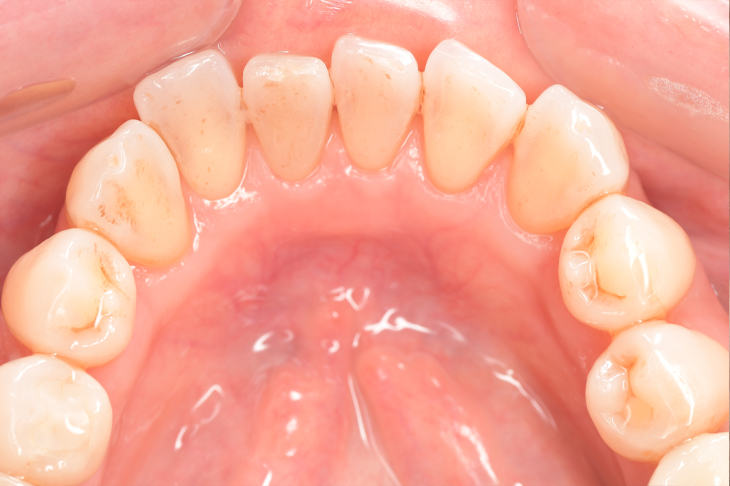

CASE 10

Before①

After①

Before②

After②

基本情報

| 年齢・性別 | 38歳・男性 |

|---|---|

| 主訴 | 下顎 歯石除去したい |

| 治療内容 | スケーリング |

| 治療期間 | 30分 |

| 治療費 | 約1,500円(保険診療) |

| リスク・副作用 | 知覚過敏、歯肉退縮 |

| 治療方針 | 歯肉縁上歯石を除去してから歯肉縁下歯石を除去します。ご自身でのプラークコントロールができるようになったら定期検診に移行します。 |

| 担当者所見 | 半年ぶりの歯科医院の受診。歯石が付きやすいためセルフケアの重要性をお伝えして、定期的にクリーニングを行います。出血率が高く炎症が強いため、今後はセルフケアを強化して歯周病治療を行います。 |